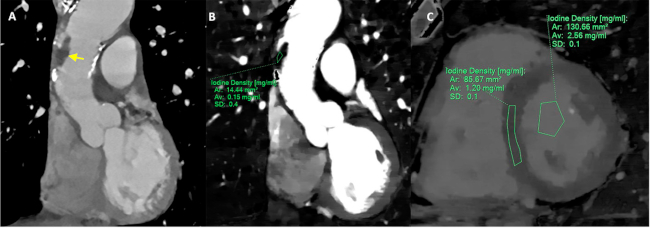

Evolucionó en forma estable y sin intercurrencias. A los 7 días se le realizó una TC cardíaca para descartar FCE donde se detectó un trombo de 7 por 21 mm a nivel de la porción tubular de la aorta sin captación de iodo (Figura 1, A y B) con orejuela izquierda y ventrículo izquierdo (VI) libres y sin particularidades. Se calculó una fracción de VEC del miocardio del 29%, (Figura 1 C), dentro de los límites normales.